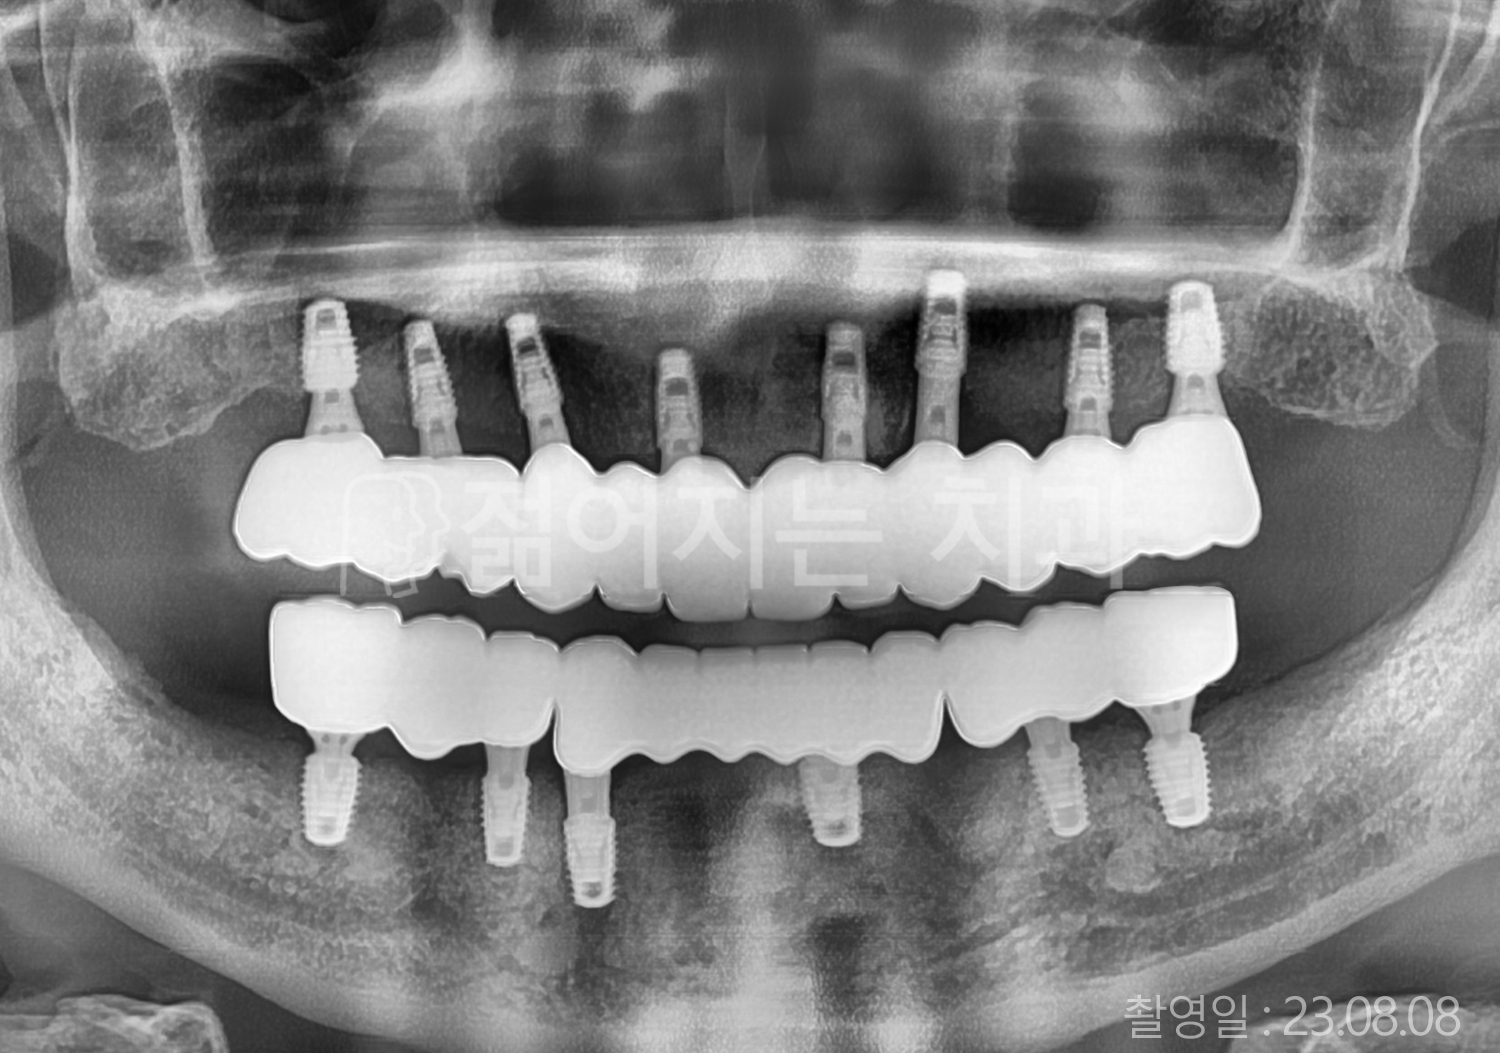

60대 고혈압, 고지혈증

전체치아 10개 이상 임플란트

60대 고혈압

70대 고혈압